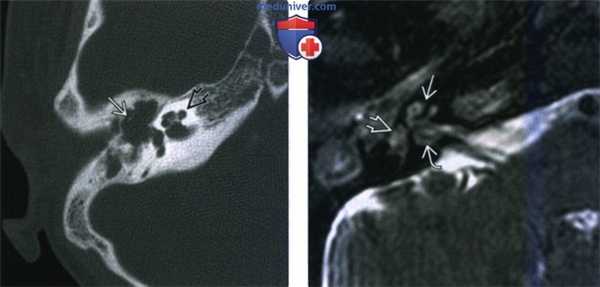

(Слева) При аксиальной КТ в костном окне у десятилетнего мальчика с отомастоидитом и деструкцией слуховых косточек визуализируется улитка, выглядящая нормальной.

(Справа) При аксиальной МРТ Т2 ВИ FS у этого же пациента пять дней спустя определяется патологический гипоинтенсивный сигнал в улитке, преддверии, и внутреннем слуховом канале, сопоставимый с замещением нормальной жидкости во внутреннем ухе фиброзно-костной тканью (ранняя стадия).

(Слева) При аксиальной МРТ Т1 ВИ С+ FS у этого же пациента соответственно определяется патологическое контрастирование среднего уха и сосцевидного отроака: улитки, преддверия, и внутреннего слухового канала.

(Справа) При аксиальной КТ в коаном окне у этого же пациента спуая год после перенесенной инфекции определяется практически тотальная оссификация улитки, сопоставимая с оссифицирующим лабиринтитом (ОЛ).